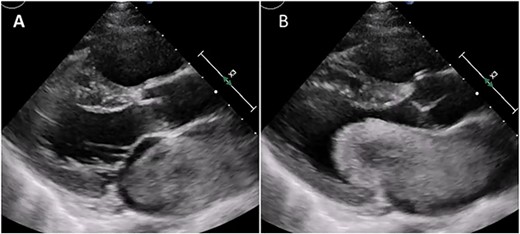

Median sternotomy was performed, and cardiopulmonary bypass was established via aortic and bicaval cannulation. Under cardiac arrest with antegrade cardioplegia perfusion, the LA was examined via the transseptal approach. The LA cavity was filled with the mass that the stalk was attached to the septal wall at the LA side, and the mass was too big and resected in pieces (Fig. 2). The mitral valve leaflet was intact, and the atrial septum was closed. Dilatated tricuspid annulus was fixed using a flexible band (Tailor Flexible band 29 mm, Abbott). After unclamping of the ascending aorta, a transesophageal echocardiogram points out moderate mitral regurgitation due to mitral annulus dilatation (Fig. 3). Cardiac arrest was performed again, and mitral annuloplasty was performed with a semi-rigid ring (Carpentier-Edwards Physio Ring II 26 mm, Edwards) via left atriotomy. His heart sinus rhythm returned to normal with successful weaning from cardiopulmonary bypass. After the transesophageal echocardiogram procedure, no evidence of the mass and residual mitral regurgitation was confirmed (Fig. 4).

Transesophageal echocardiogram after mitral annuloplasty. There was no residual mitral regurgitation.